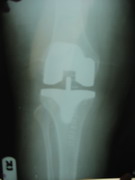

Knee Joint Replacement